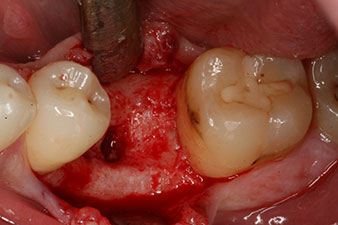

periimplantario con virutas de hueso autógeno

Figura 5: Para obtener un contorno de tejido periimplantario favorable, en primer lugar es preciso compensar la carencia de hueso periimplantario con virutas de hueso autógeno.

Este habría permitido una cicatrización abierta o incluso un tratamiento inmediato. Sin embargo, como no se disponía de suficiente hueso en la parte crestal del implante, el área se aumentó con las virutas óseas recopiladas durante la preparación del lecho del implante y se suturó para que no penetrara saliva.